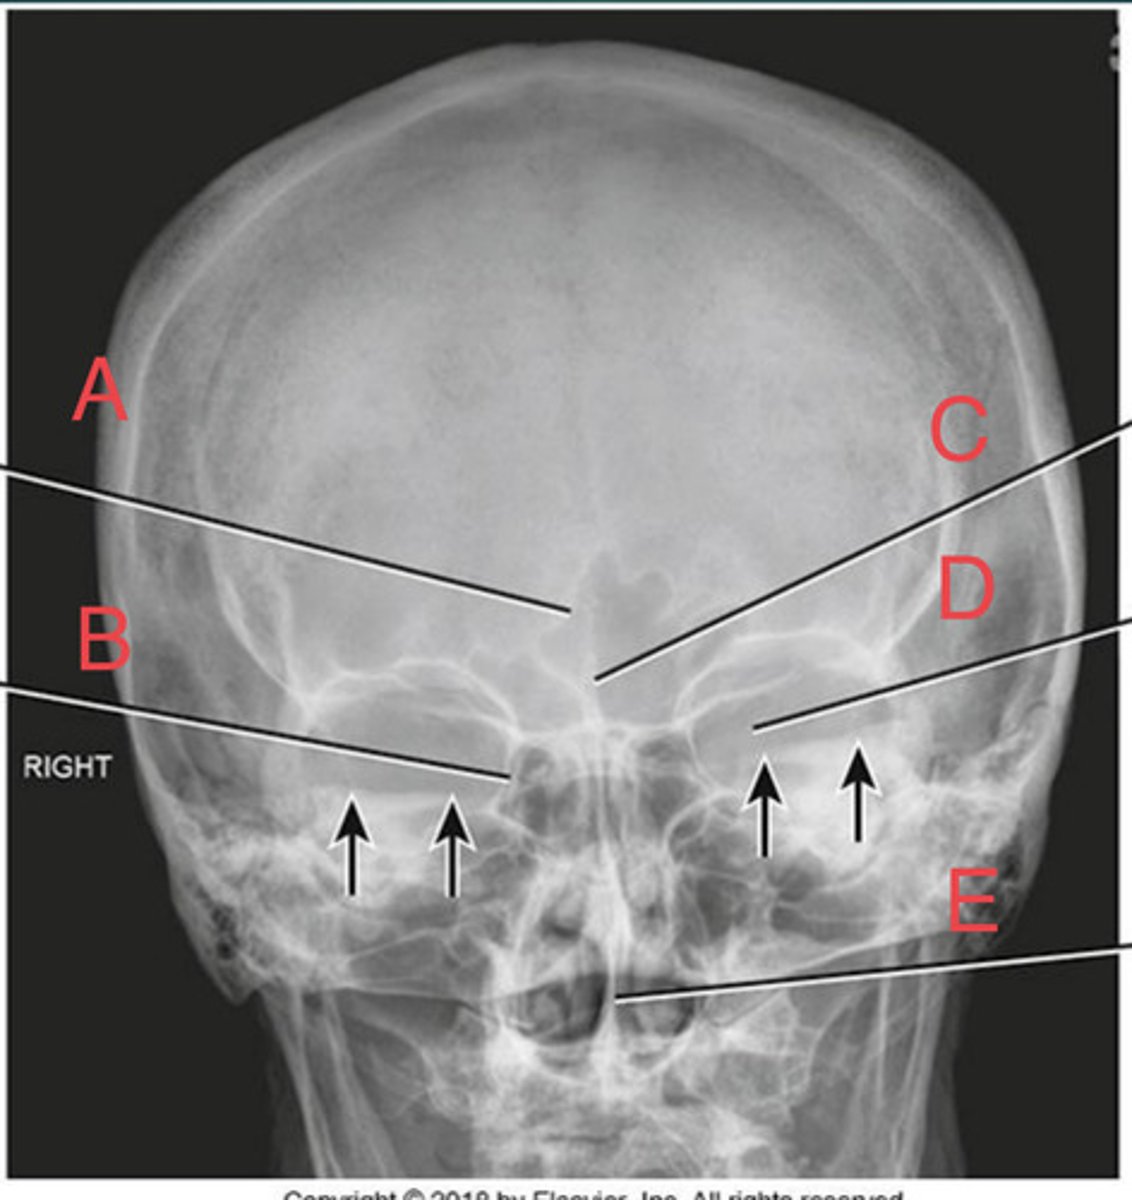

Open Mouth Waters Sinuses

What projection?

R Sphenoid sinus of sphenoid bone

A.

L frontal sinus of frontal bone

B.

Nasal fossa

C.

L. Maxillary sinus Of maxilla

D.

L. alveolar process of mandible

E.

L petrous ridge of temporal bone

F.

L petrous ridge of temporal bone

I.